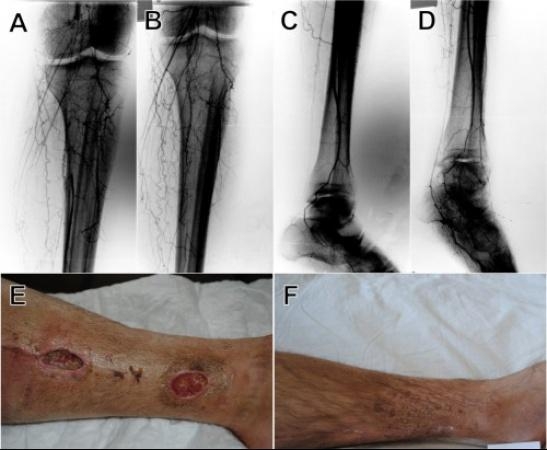

Pirmą kartą Lietuvoje: kamieninės ląstelės išgelbėjo nuo galūnių amputacijos